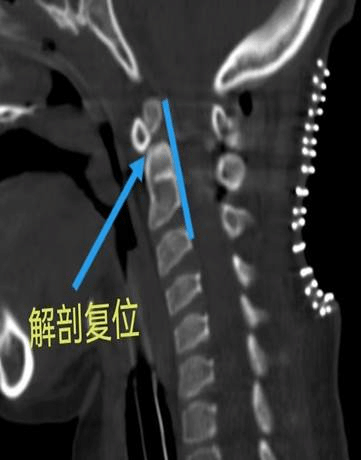

手术及时顺利的开展,术中赵伟副主任精细操作,解剖复位、重建寰枢椎稳定性。术后患儿返回ICU继续治疗,经近一个月的术后康复治疗,患儿完全恢复自主呼吸,四肢肌力也有了一定程度的恢复。

术后磁共振,脊髓压迫得到解除术后颈椎CT矢状位寰枢椎解剖复位